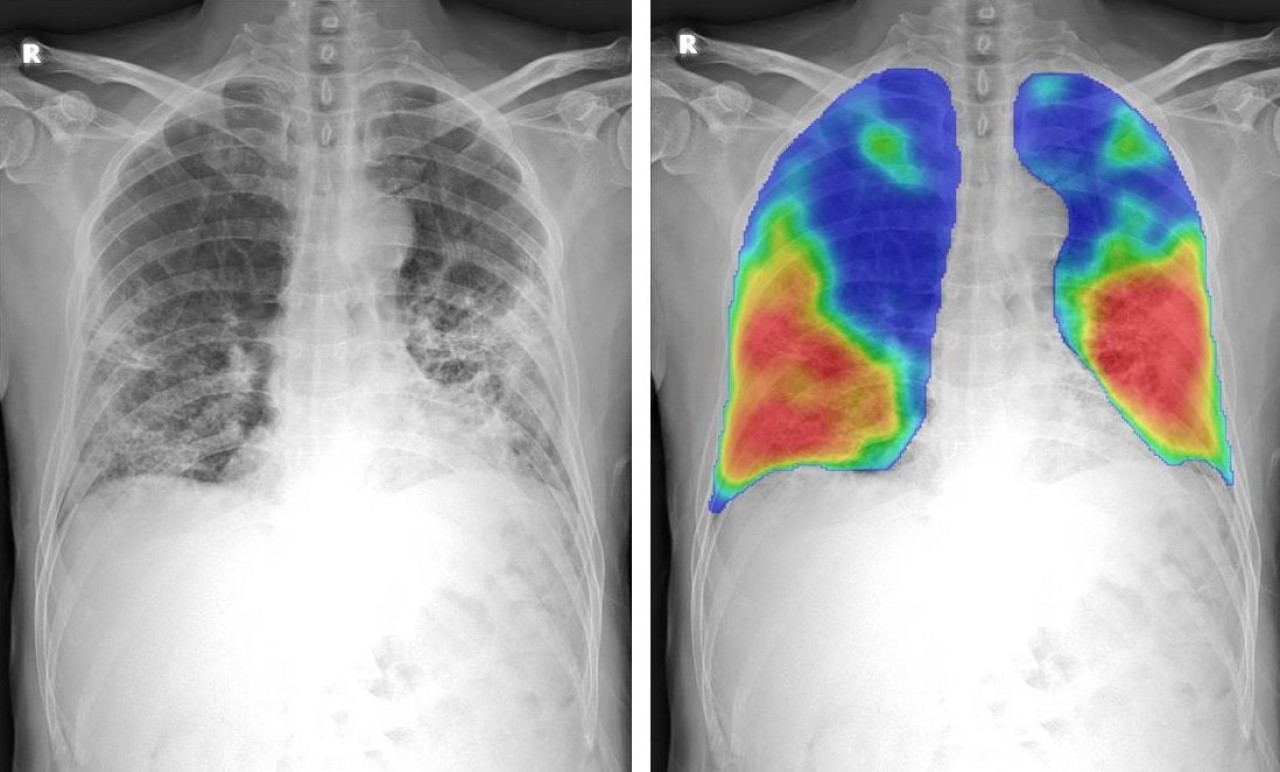

Ancak bu durum yakında tamamen değişebilir. Yeni bir çalışmada, Iowa Üniversitesi'ndeki bilim insanları tarafından karşılaştırmalı öğrenme modeli adı verilen yeni bir saptama projesi geliştirildi. Bu yeni model, 3D BT görüntülerinden oluşturulan kompozit 2D görüntüleri kullanarak COVID-19 hastalarında riskli akciğer fonksiyonunun nasıl tespit edileceğini gösterir. Transfer öğrenme adı verilen başka bir teknik ise daha sonra bir BT taramasından akciğer diyagnostik bilgilerini bir göğüs röntgenine aktarır. Böylece göğüs röntgeni ekipmanının, sanki bu hastalar bir BT taraması kullanmış gibi anormallikleri tespit etmesine olanak tanır.

Frontiers in Physiology dergisinde yakın zamanda yayınlanan çalışmada araştırmacılar, karşılaştırmalı öğrenme modellerinin, COVID-19 hastalarında akciğer fonksiyonunun erken bir aşaması olan küçük hava yolları hastalığını tespit etmek için nasıl uygulanabileceğini gösterdiler. COVID-19 hastalarının modelleri, küçük hava yolları hastalığı olanları daha ileri solunum sorunları olanlardan ayırarak, tehlikeye giren akciğer fonksiyonunun ciddiyetini ayırt edebiliyordu.

Araştırmacılar modellemelerini, COVID ile enfekte olan ve solunum sorunları nedeniyle teşhis için hastanelere giden 100 kişinin BT taramalarına dayandırdı.

Araştırmacı ekip, BT akciğer taramalarında hasta nefes aldığında ve hasta nefes verdiğinde olmak üzere iki aralıkta veri noktaları topladı. Araştırmacılar, karşılaştırmalı öğrenme modelini oluştururken sonuçlarını virüs bulaşmamış bir kontrol grubuyla karşılaştırdı.